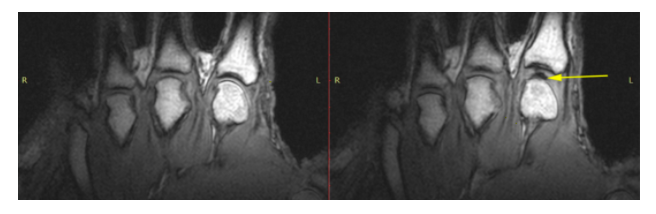

为此他们动用了核磁共振扫描仪,对掰扯的关节进行可视化的观察。

图片来源:PLoS ONE

当手指关节被拉伸时,关节腔中确实产生了一个黑色的气体空腔。但在听到咔的一声后,气体空腔仍然存在。

如果是破裂产生的声音,那么空腔应该消失不见。